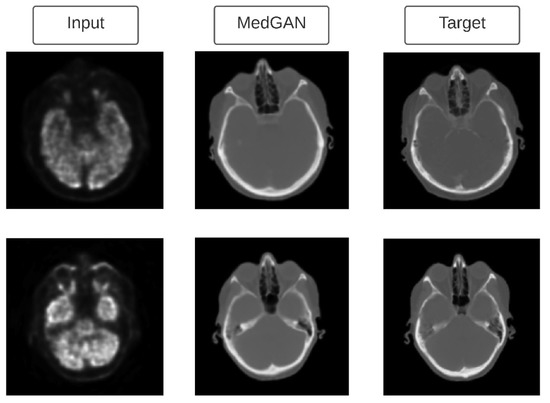

| Armanious et al. [116] | PET, CT images (brain) | Multi-modal dataset | Developed MedGAN architecture which consists of a cascade of UNet blocks to obtain sharper translated images (CasNet) along with Gatys et al.’s [101] style transfer losses. |